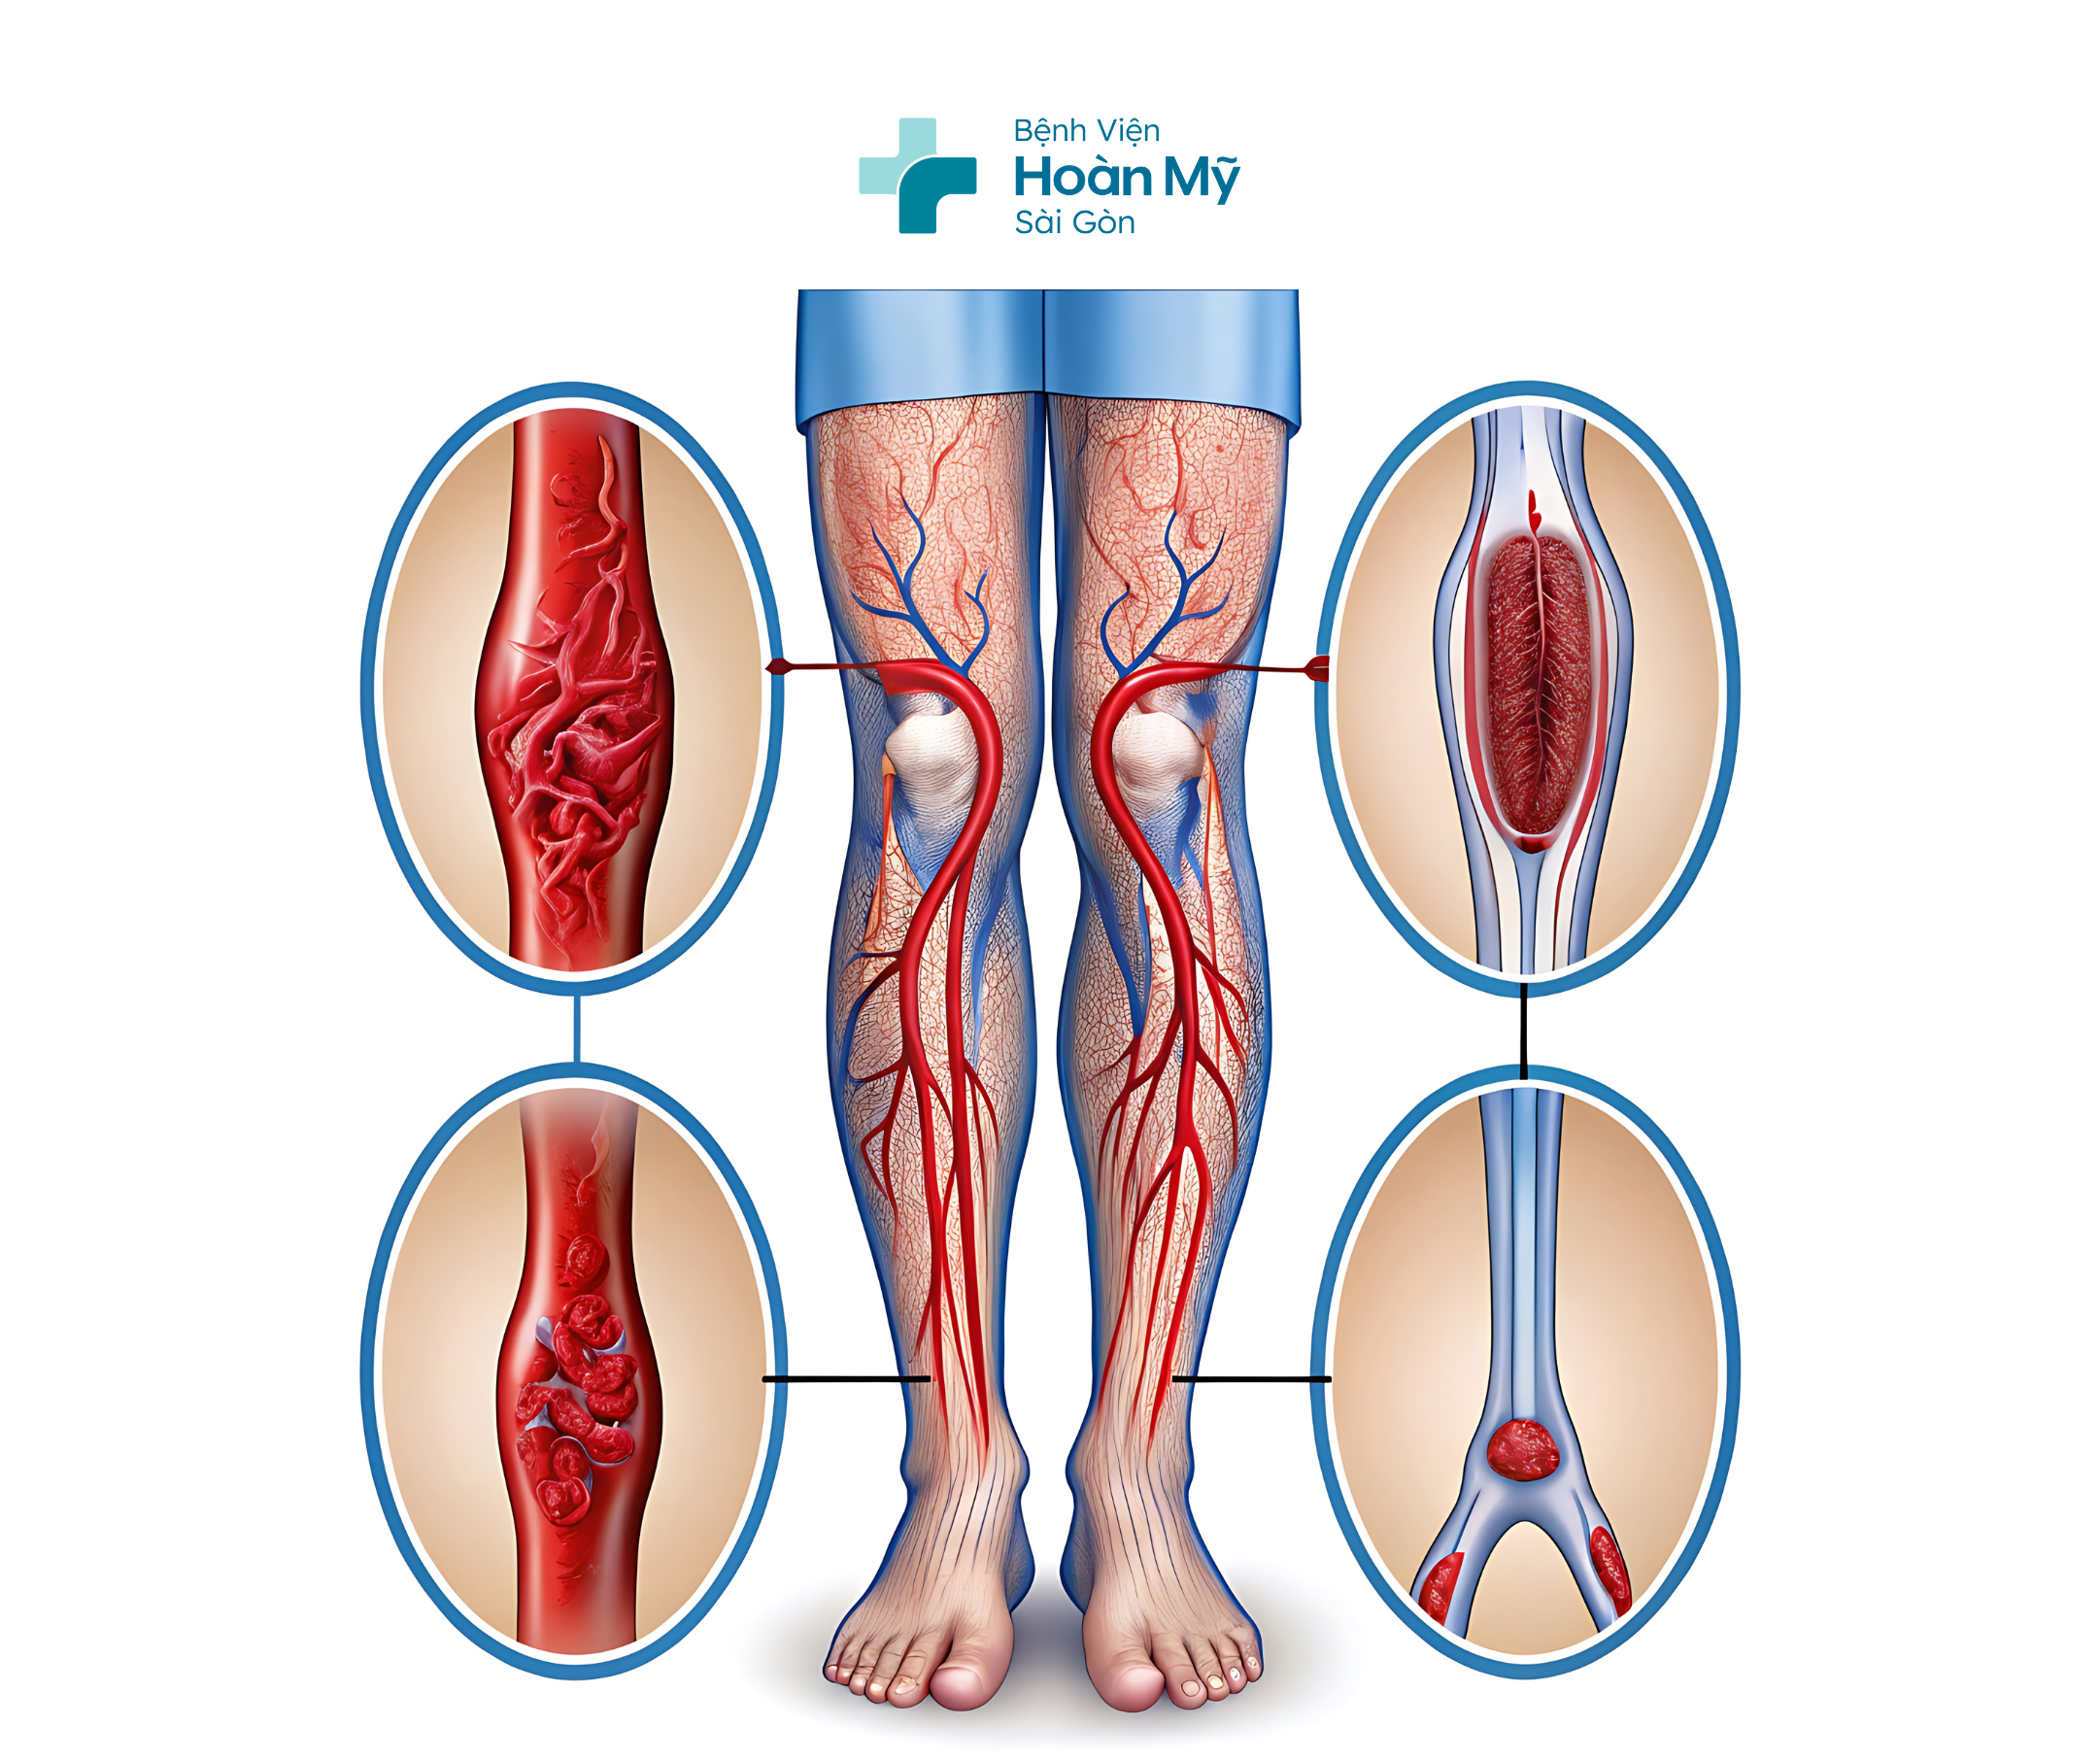

Hình ảnh CT cho thấy người bệnh bị tắc động mạch ở chân phải

BS. Thiên chia sẻ bệnh tắc động mạch chi dưới, hay còn gọi là bệnh động mạch chi dưới, là tình trạng hẹp hoặc tắc nghẽn các động mạch cung cấp máu cho chi dưới, thường do xơ vữa động mạch. Đây là bệnh lý phổ biến ở người cao tuổi và có thể dẫn đến các biến chứng nghiêm trọng như hoại tử hoặc phải cắt cụt chi nếu không được phát hiện và điều trị kịp thời. Bác sĩ khuyến cáo người bệnh cần lưu ý: